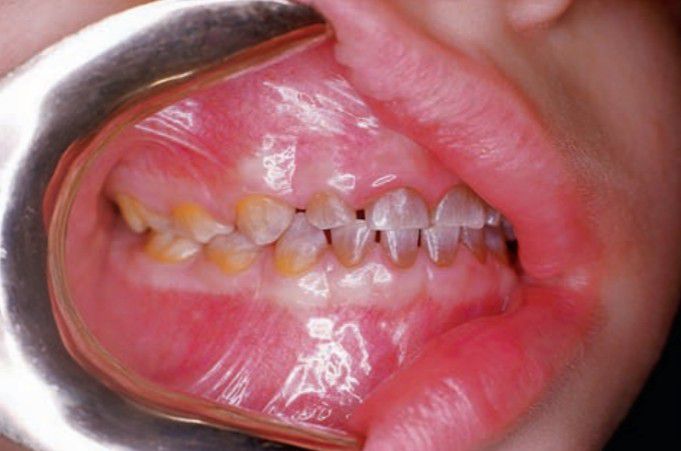

Tetracycline staining

Tetracycline stain. Note the yellow color (tetracycline) of the posterior teeth and the gray color of the anterior teeth, in which oxidation of endogenous tetracycline has occurred